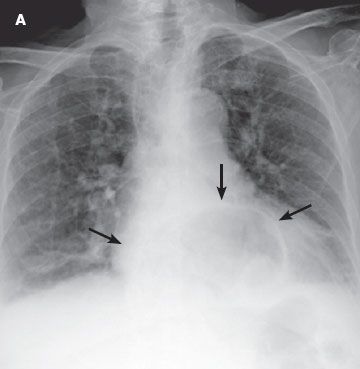

Physical findings were unremarkable. Radiographs of the chest and abdomen showed a gastric bubble in the left lower thoracic cavity (A). A barium swallow showed the stomach within the thorax (B).

An organoaxial volvulus is a type of gastric volvulus-a rare but serious disorder-in which the stomach rotates superiorly along its long axis. The rotation must be 180 degrees or greater and is usually associated with diaphragmatic defects. The rotation causes the greater curvature of the stomach to be superior to the lesser curvature; as a result, the stomach appears upside down. About 60% of cases are organoaxial and 30% are mesenteroaxial, in which the stomach rotates along its short axis. This less common form is usually associated with ligamentous laxity. The remaining 10% of cases are a mixed type.1 The disorder can be further classified as subdiaphragmatic, or primary (33% of cases), in which the cause is usually congenital, or as supradiaphragmatic, or secondary (67% of cases), which is generally caused by trauma or associated with diaphragmatic defects.2